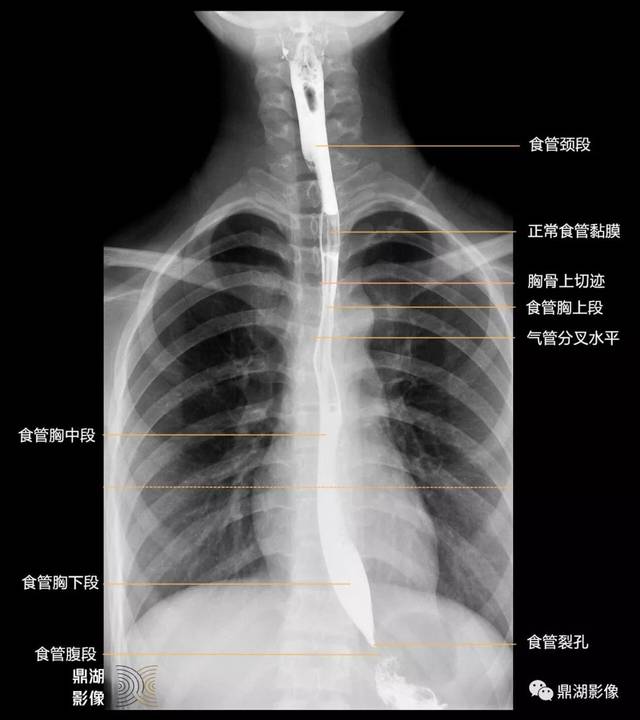

x线高清图谱食管造影解剖

x线高清图谱 | 食管造影解剖

5 分钟读懂消化道造影片(食管篇)